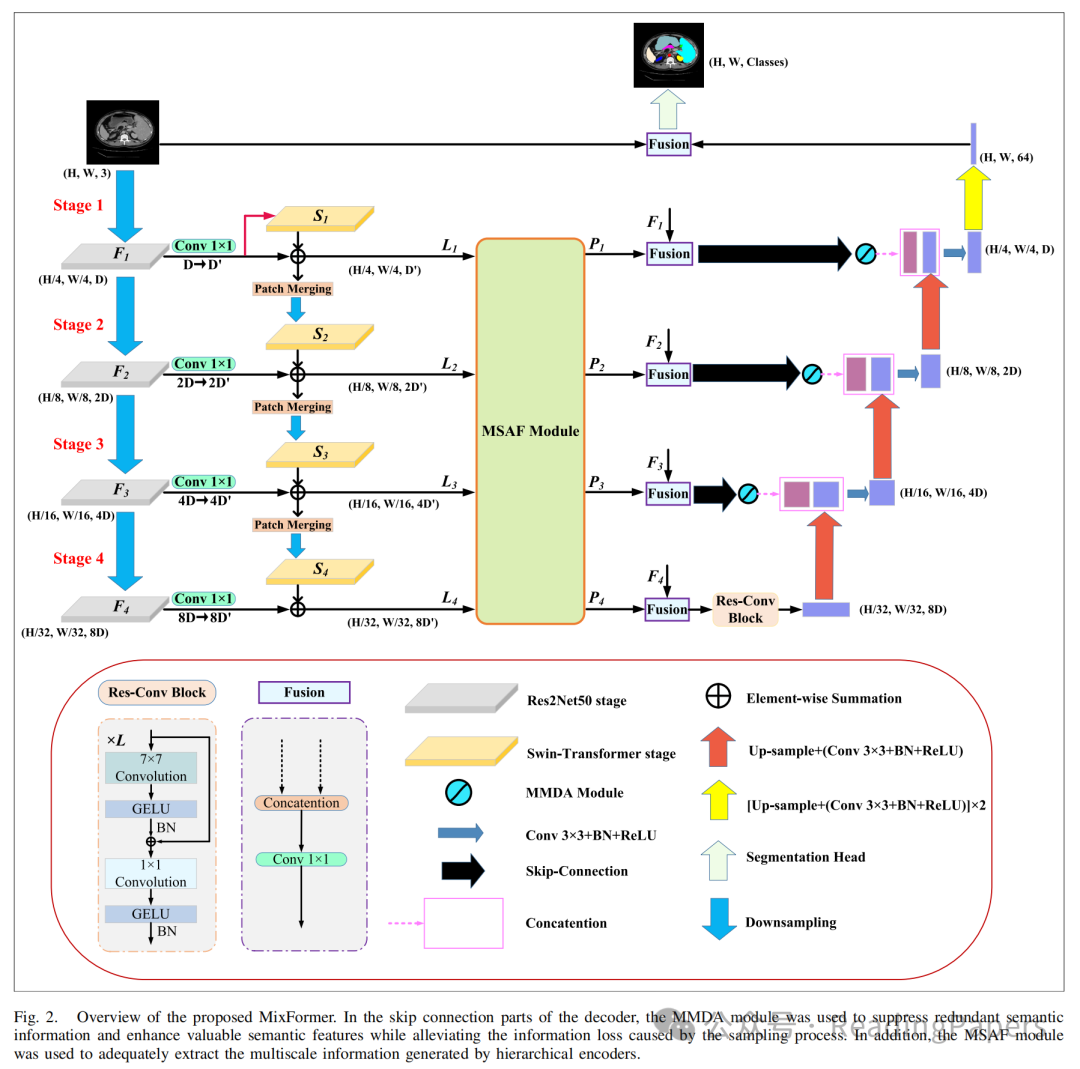

A. 网络结构

所提出的MixFormer遵循典型的U形架构,主要由编码器、解码器和跳跃连接组成。编码器由两部分组成:基于CNN-Transformer的混合特征提取骨干网络和MSAF模型。解码器由基本的CNN单元组成。此外,在跳跃连接部分引入了混合多分支扩张注意力(MMDA)模块。在该方法中,混合特征提取器用于从Transformer和CNN中获取多层视觉特征,分别包含全局和局部线索。MSAF机制进一步在多个尺度之间交互语义信息,以获得增强的特征表示。为了获得更好的上采样性能,作者在编码器的最深层实现了Res-Conv块,以进一步加强全局特征表示。最后,作者将MMDA机制集成到跳跃连接中,有效地将融合的语义特征传递到解码器,以进行最终的分割预测。

B. 混合特征提取骨干网络

在MixFormer中,作者使用了一种混合编码器框架,该框架由Swin Transformer和Res2Net50组成,用于在编码阶段提取特征。这使得编码器能够在每个尺度上有效捕捉局部细节和全局上下文信息。Res2Net50在提取多尺度特征方面优于传统的CNN。此外,Swin Transformer在定义的窗口内对图像块进行自注意力计算,其计算开销与图像大小呈线性关系,这与ViT在整个图像块集上进行自注意力计算形成对比。

在本研究中,通过使用Res2Net50网络作为局部细节提取器,作者有效地分割了原始图像(),以获得不同分辨率的特征金字塔输出到。然后,这些输出的通道维度通过1×1卷积操作映射到与相应Swin Transformer块相同的嵌入维度,并作为补偿Res2Net模型在不同阶段缺失的长距离依赖关系输入到Swin Transformer模块中。在作者的方法中,有四个下采样阶段用于获取局部语义信息。每个阶段的特征图输出大小为、、和,通道数分别为、、和。

为了弥补Res2Net模型在全局上下文信息方面的缺失,作者将局部细节特征图()划分为图像块,并将其输入到Swin Transformer中。Swin Transformer有四个阶段,每个阶段包含特定数量的块,能够建模长距离依赖关系。这使得作者能够获得四个阶段的特征表示到,其中包含全局上下文信息。此外,作者在每个阶段采用了图像块合并方法,将特征图的通道维度加倍,同时降低分辨率,然后将其输入到下一阶段的Swin Transformer块中。Swin Transformer四个阶段的特征图分辨率分别为、、和,通道数分别为、、和。最后,局部空间信息()和全局语义信息()在相应层次上连接,以获得四个尺度上的增强特征表示到。然后,这些特征表示被输入到MSAF模型中进行不同尺度之间的信息交互。

C. MSAF模型

已经证明,多尺度信号在分割具有复杂位置和大小变化的器官时极为有价值。为了解决多尺度特征之间的语义信息交互问题,作者利用了MSAF模块。该模块包括四个步骤:图像块匹配、尺度融合、尺度分割和图像块反转,这些步骤共同实现了跨尺度依赖关系的建立。MSAF模块的网络结构如图6所示。

D. 混合多分支扩张注意力模型

神经网络中浅层和深层特征具有不同的表示能力。因此,迫切需要寻求一种解决方案,以有效弥合编码和解码阶段相应特征之间的语义差距,同时最小化由采样过程引发的信息丢失。为此,作者引入了一种混合多分支扩张注意力(MMDA)模型,从三个维度(即通道、空间和全局上下文)映射特征,综合优化提取特征的信息丢失。该方法有效地减少了提取特征中的信息丢失,从而帮助解码器准确恢复特征图的原始分辨率。作者将MSAF每一层(除了最深层的下采样层)提取的特征图与相应的CNN特征金字塔输出融合。然后,通过跳跃连接将该组合输入到MMDA模块中进行特征提取。最终,该方法实现了与相应解码器层的和谐特征融合。MMDA模型由三个单元组成,包括全局自注意力单元、通道注意力单元和空间注意力单元,如图7所示。

E. 解码器

为了增强有效感受野并使其更容易混合远距离上下文信息,融合后的特征图被输入到最深层的下采样层的Res-Conv块中。如图2所示,Res-Conv块由层(本文中设置为7)组成,通过深度卷积(即核大小)和点卷积(即核大小)混合空间位置和通道位置,进一步获取上下文依赖关系。此外,深度卷积中的组通道数等于输入特征图的通道数,并且每个卷积操作都应用了高斯误差线性单元(GeLU)激活和批归一化,如下所示:

最后,作者采用双线性插值方法对特征图进行上采样。解码器由四个阶段组成,每个阶段包括一个典型的卷积块、一个上采样操作和ReLU激活函数。解码器首先接收低分辨率()的融合特征图,经过四次连续的上采样操作后生成高分辨率()的特征图。然后,重建的特征图通过分割头中的卷积生成最终的分割结果,其中通道数与预测类别数相同。